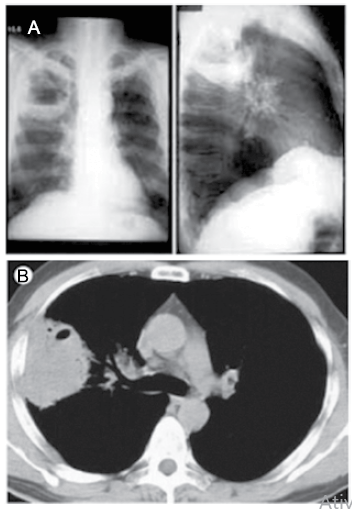

Mulher de 85 anos, portadora de distúrbio crônico da deglutição, com vários episódios anteriores de aspiração e engasgos, procurou o pronto-socorro por apresentar febre alta, tosse produtiva (“catarro espesso”), dor torácica à direita e dispneia há uma semana. Na admissão: temp. ax. 38,0 ºC, sat.O2: 90%; PA: 125x85 mmHg; FC: 98 bpm. Após as medidas iniciais de estabilização e reanimação, foram realizados exames de imagem demonstrados a seguir.

Com base nos dados clínicos e exames demonstrados, o diagnóstico da paciente é: